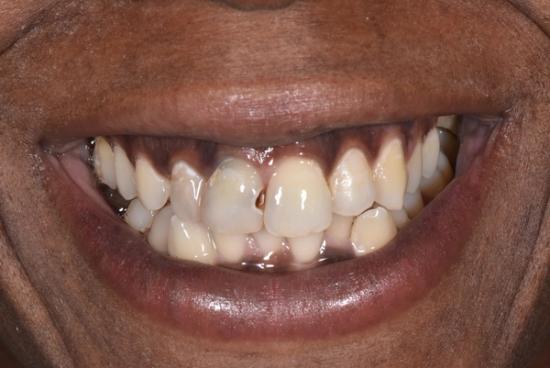

Before Photo